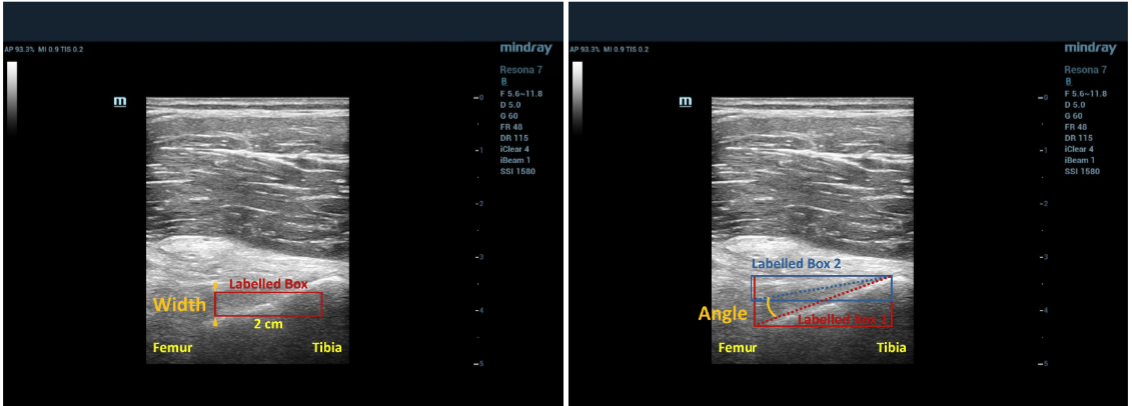

- 2025.11: New Journal Paper A Novel Deep Learning Based Automatic Ultrasonic Posterior Cruciate Ligament Clinical Assessment Tool Accepted by npj Artificial Intelligence.

Real time musculoskeletal ultrasound image annotations